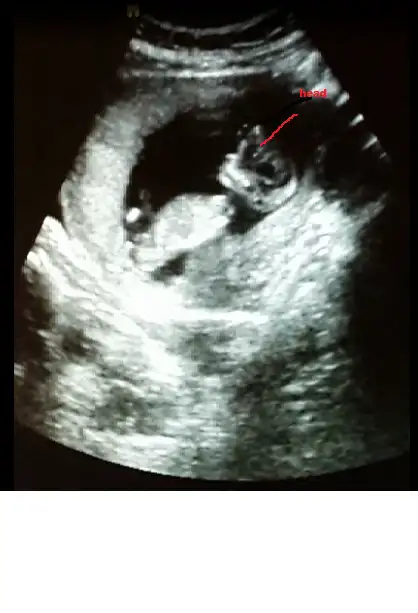

Gijnij merhaba ben seni ve buranin sıkı takipcilerindenim benim de 2 kizim var ALLAH nasip ederse 3 cuye hamileyim 14 haftalik rica etsem resimi eklesem bana yorum edermisin image.webp

ben mesaj atmıştım sana ama sorun oldu gitmedi sanırım. bu fotoda ben nubu çözemedim canım

Sagolasin canim yorumun icin ben 13 haftalikken gittigimde ozeldeki doktor yuzde yetmis erkek demisti 2 li icinde devlete gittim soylemedi ondan merak ettim sordum cnm bu arada senin bana msjin gelmedi gelseydi soylerdim cnm

Bebeğin kız canım hayırlı olsun inşallah

bak buda bacak arası. ama video çekmiştik sanki pipi var gibi geldi bana. acaba kordon mu o? çok kalındı zaten keşke videoyu gönderebilsem sana :).. bu arada yorumun için çok teşekkür ederim canım:KK68:

• tp.webp

tp.webp

12,6 KB · Görüntüleme: 194

Canım kızda da erkekte de bu haftalarda çıkıntı oluyor sadece kızın çıkıntılı karşıya bakıyor erkeğin yukarı doğru senin o pipi gibi gösterdiğin karşıya bakıyor kız gibi yani yinede yanılma payı vardır mutlaka